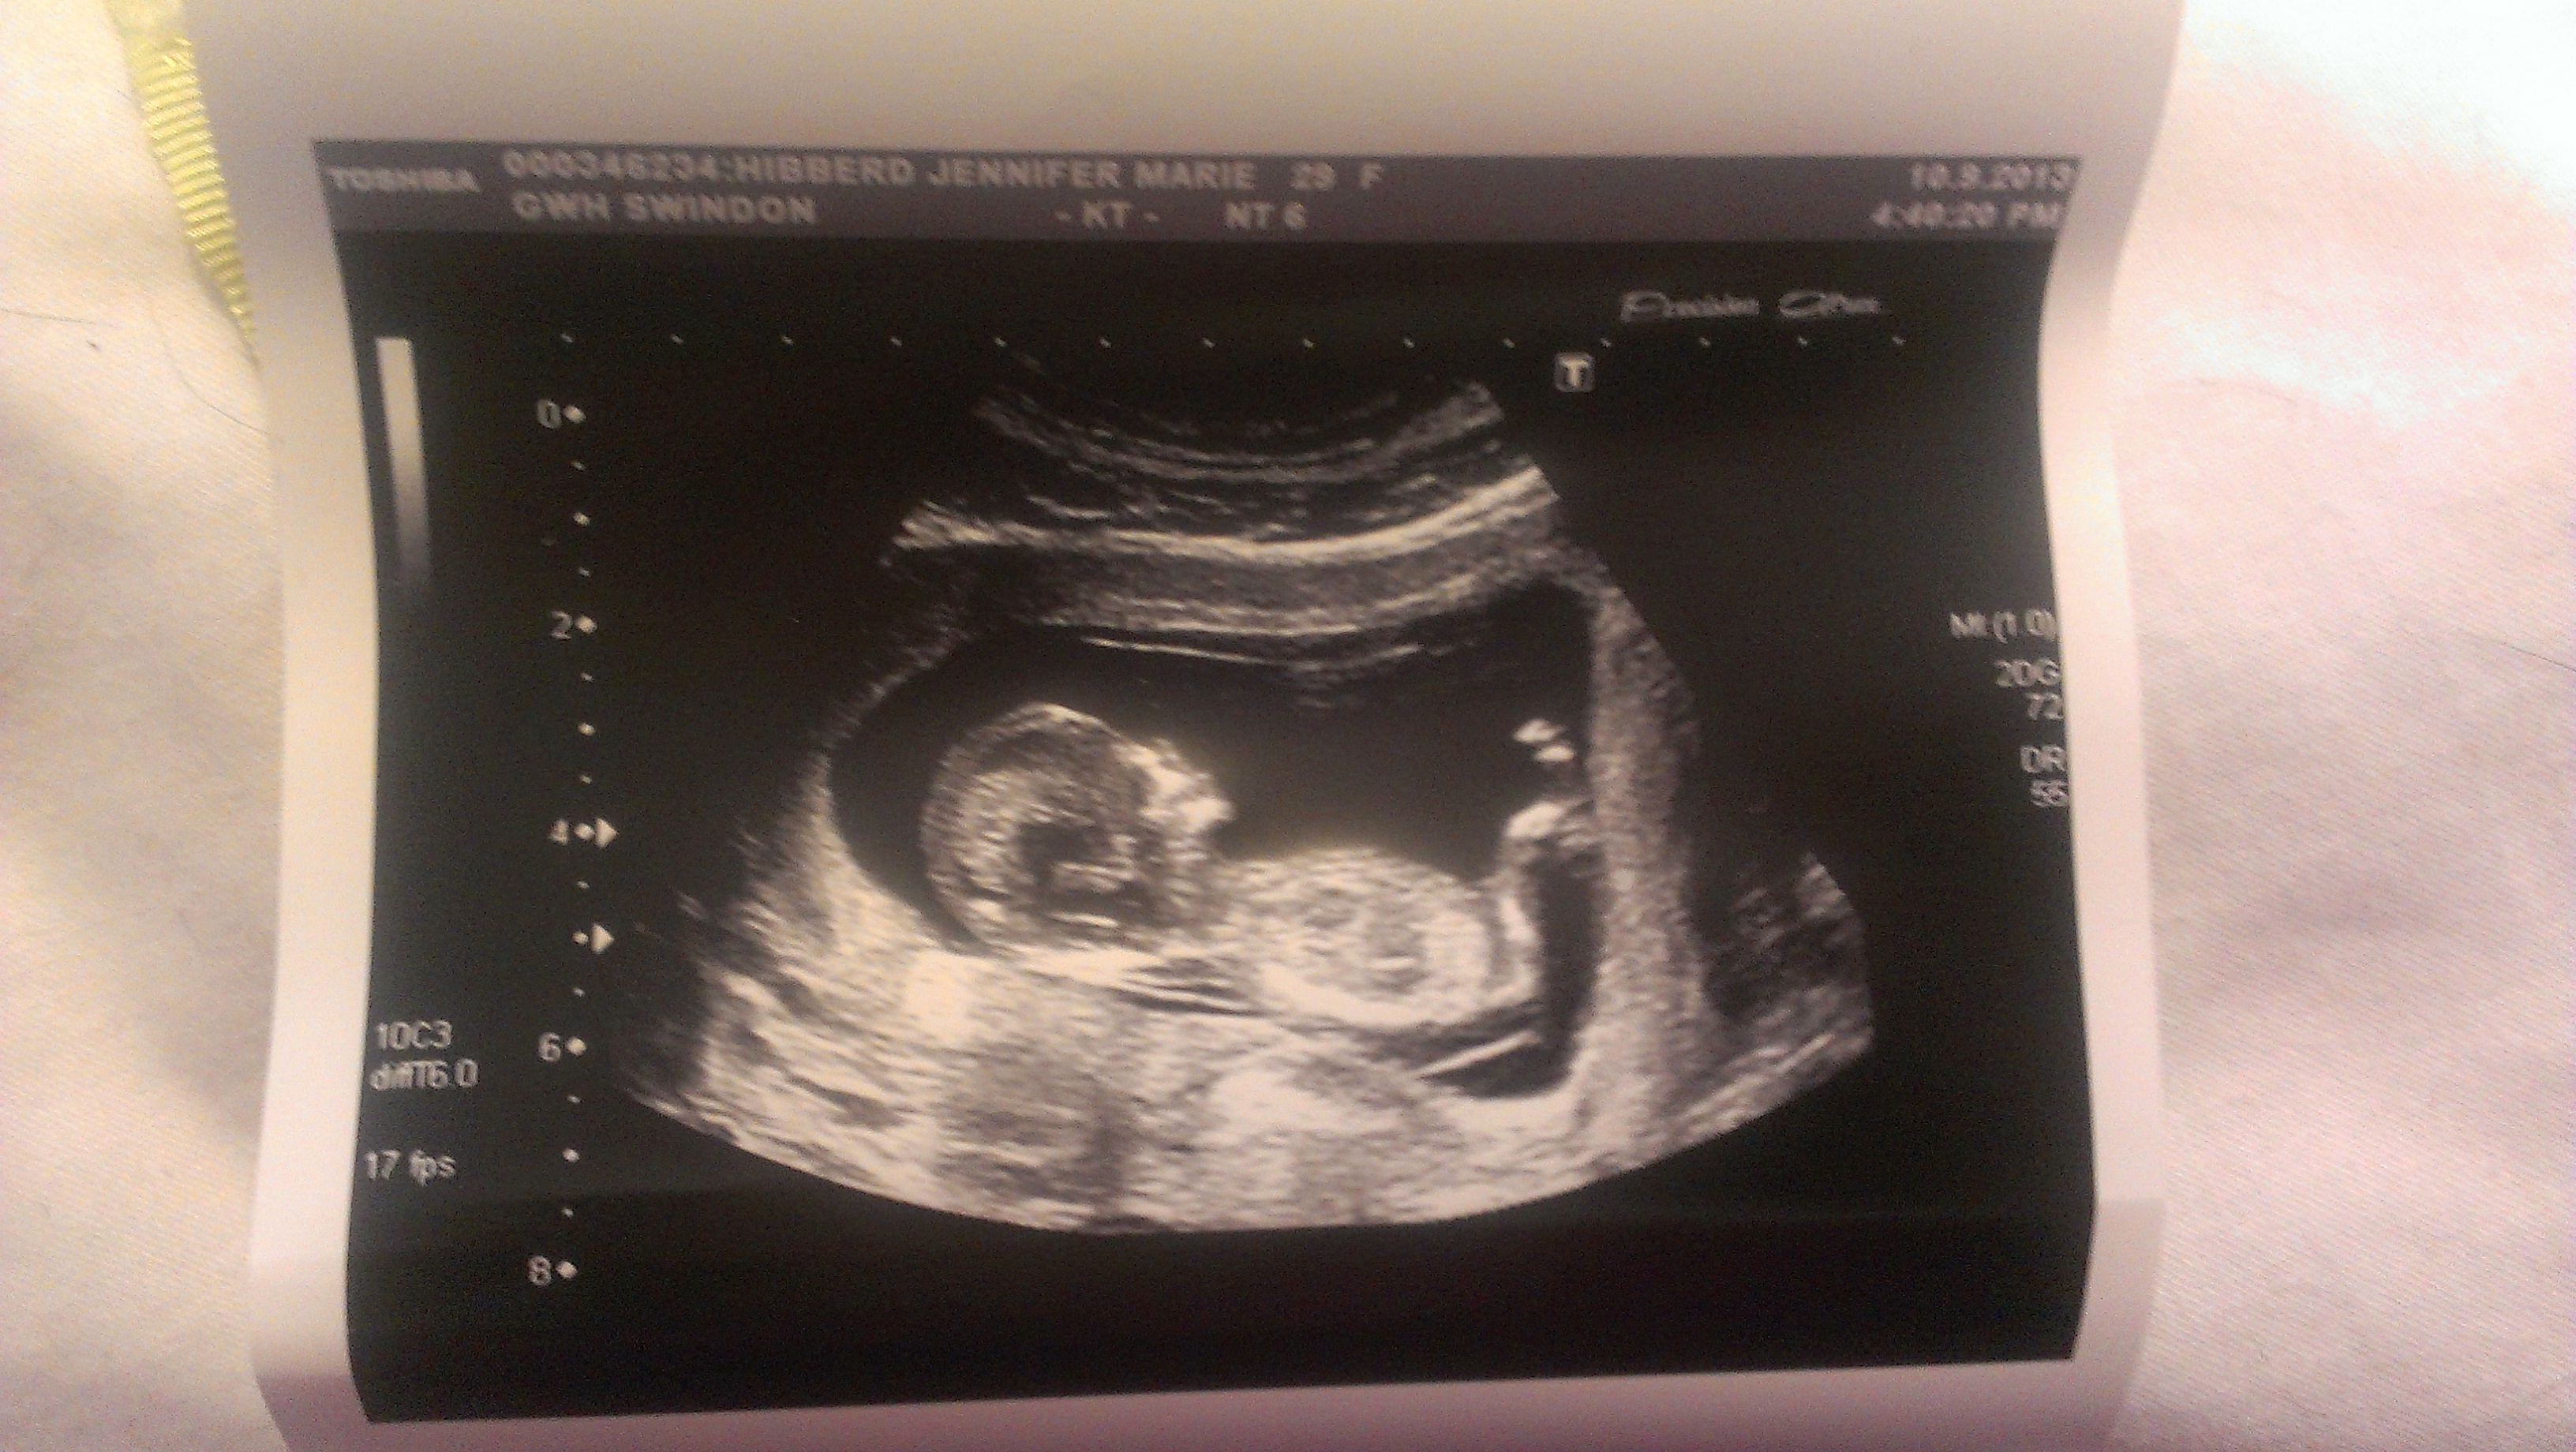

Attachment 14007Attachment 14008

I'm new to this forum so hello! I've read about the nub theory online and wondered if any experienced eyes would have a guess at my baby's gender looking at my scan pics! I hope I've attached the pics correctly.